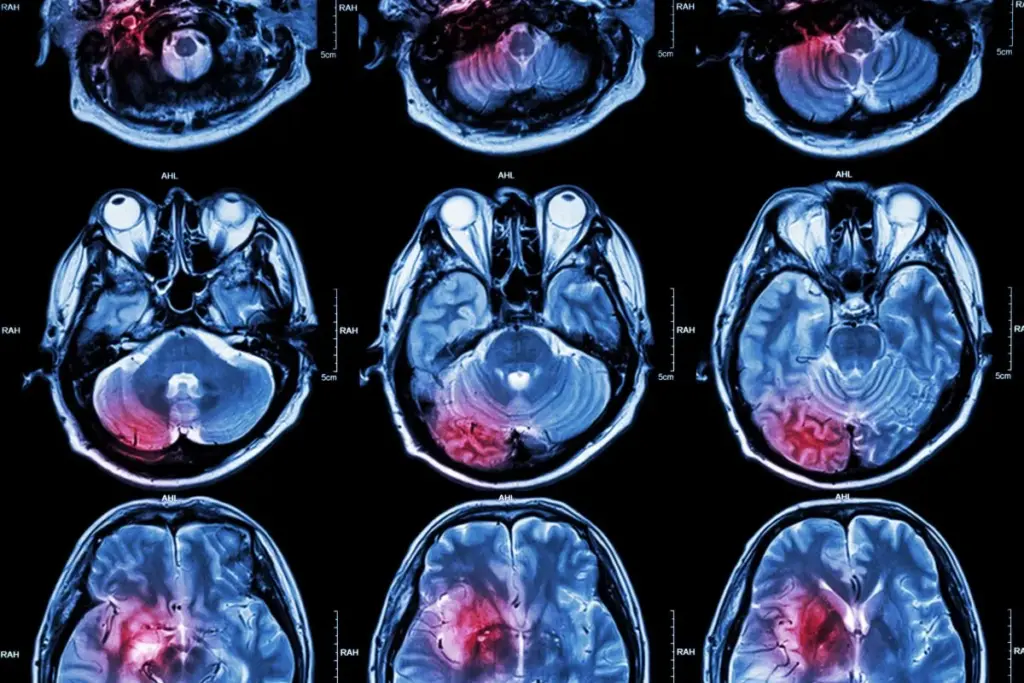

Brain tumors can start in any part of the brain or skull. This includes the protective lining and the underside of the brain (skull base). They can also form in the brainstem, sinuses, and nasal cavity. The brain‘s complex structure makes it possible for tumors to develop in different areas.

The brain is made up of several parts. These include the cerebrum, cerebellum, and brainstem. Each part can be a possible site for tumor growth. Knowing where brain tumors come from is key to diagnosing and treating them well.

Knowing the brain’s layout is key to finding where tumors might grow. The brain is a complex organ with different parts handling various tasks. Tumors can pop up in any area, messing with the brain’s functions.